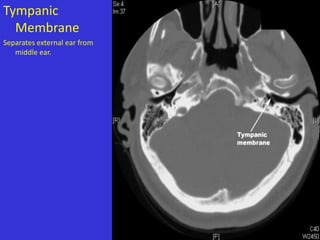

Tympanic

Membrane

Separates external ear from

middle ear.